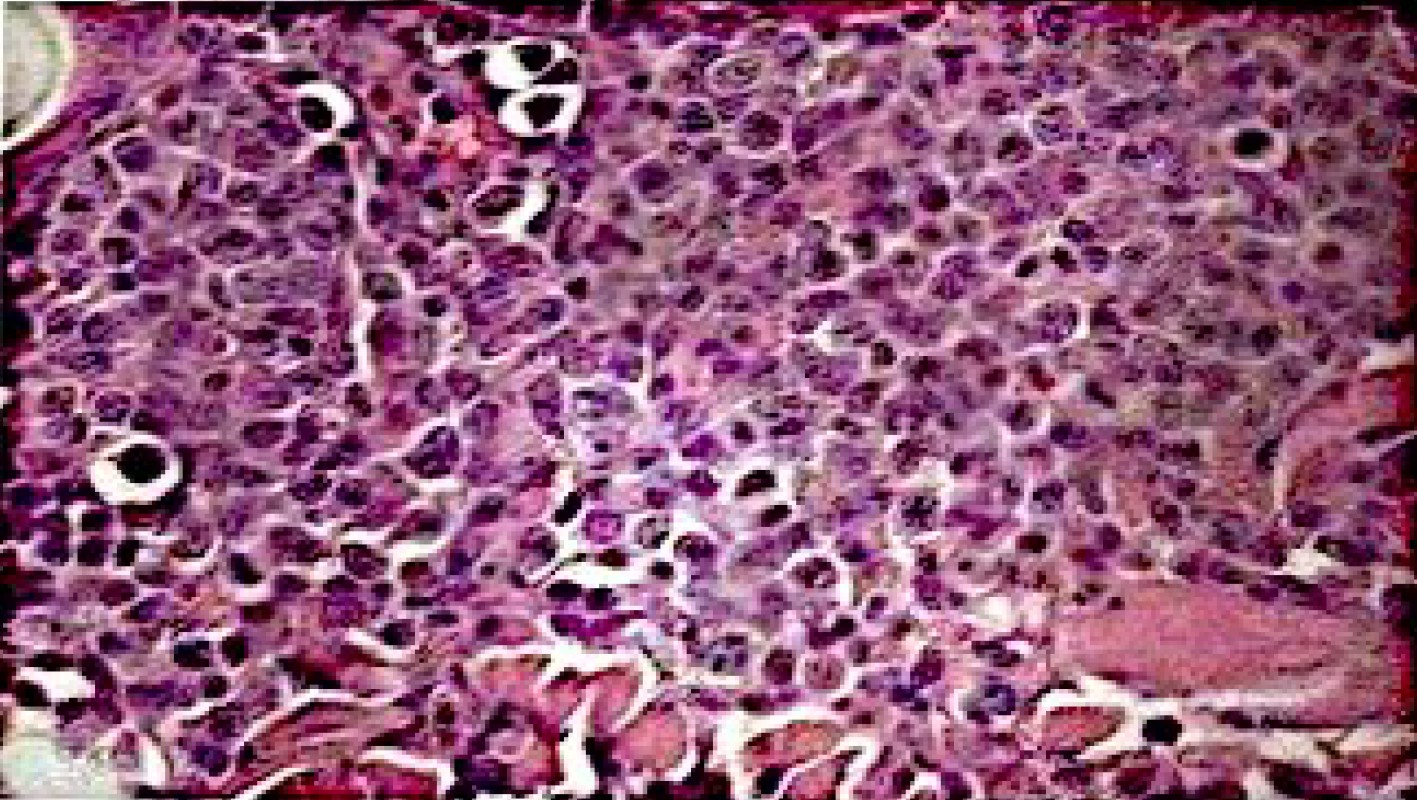

病理組織切片,確認淋巴瘤細胞型態

貝果的右後肢掌骨內側發現表面潮紅、直徑約2公分的團塊,經組織病理診斷為皮膚型非親上皮性T細胞淋巴瘤,中至大淋巴球。手術切除後,接受三次口服Lomustine(CCNU)的預防性治療,並於療程結束後,以癌識優®檢測評估治療效果及追蹤癌症,貝果目前狀況穩定。